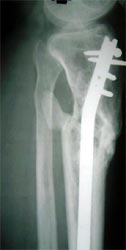

图1-1 X线片显示胫骨中上段粉碎骨折,有骨缺损、骨不连,

骨质吸收,骨折端变尖,断端硬化